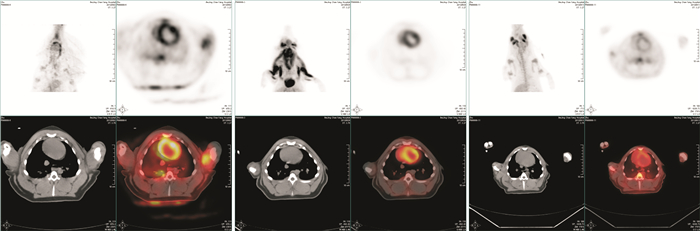

两组实验动物基础状态和ROSC 4 h,24 h左心室对18F-FDG的SUVmax)值比较,见表 2,图 3。

| 组别 | 基础SUVmax | ROSC 4 h SUVmax | ROSC 24 h SUVmax |

| VFCA组 | 2.6±0.2 | 1.9±0.3ab | 2.4±0.6b |

| ACA组 | 2.7±0.3 | 1.0±0.4a | 1.2±0.5a |

| 注; 组内与基础状态比较,aP<0.01;组间与ACA比较,bP<0.01 | |||

| A,基础状态;B,VFCA组ROSC4 h PET心脏检查图像;C,ACA组ROSC4 h PET心脏检查图像。A-C图中左上为PET影像,左下为融合影像,右侧为CT影像。在PET影像中,环状高密度区代表心脏的左心室。 图 3 实验动物行PET心脏检查图像 Figure 3 Cardiac examination images using PET |

细胞代谢活动的存在是心肌细胞存活最可靠的标志,目前认为18F-脱氧葡萄糖正电子发射型计算机断层显像(18F-FDG-PET)是目前判断心肌存活最准确的方法,被称为无创方法检查心肌活性的“金标准”[15]。正常静息状态下,心肌代谢主要以游离脂肪酸和葡萄糖的氧化作为能量,在禁食或者运动状态下,葡萄糖成为心肌的唯一能量来源,因此如果细胞内存在葡萄糖代谢就能够证明心肌细胞是存活心肌。18F-FDG的结构式与葡萄糖很相似,仅2位上的羟基被18F取代,18F-FDG与葡萄糖竞争,经己糖激酶介导的摄取和磷酸化而生成18F-FDG -6-PO4。18F-FDG -6-PO4不再参加进一步代谢,最终滞留在心肌细胞中内,显像时出现放射性浓聚。我们的研究就是利用PET这一判断心肌细胞是否存活的金标准通过计算左心室的SUVmax)值来比较窒息与室颤导致的CA心肌代谢的特点。我们的研究结果提示,在基础状态相同的状况下,经过不同方法的CA模型制作以及成功ROSC后4 h,室颤模型的心肌代谢SUVmax)值要明显高于窒息模型,说明虽然室颤直接损伤的是心脏,但是心肌细胞损伤程度要远低于窒息模型。由于单独使用PET代谢性检查不能明确发生的心肌损伤是心肌顿抑还是心肌坏死[16],所以本研究在动物ROSC 24 h后再次进行了心肌PET影像检查。本研究结果发现,室颤组动物在ROSC后24 h,心肌的SUVmax)值已经恢复到正常水平,所以从心肌代谢的角度上评估已经完全恢复,这就说明了室颤导致CA,ROSC后存在心肌顿抑,这与先前研究也是一致的[17]。而窒息导致CA细胞代谢严重降低以及在ROSC后24 h恢复困难,可能已经发生了严重的细胞坏死或者凋亡,这可能与窒息过程中心肌细胞内线粒体发生严重损伤导致细胞呼吸代谢链发生不可逆性损伤有关[18]。